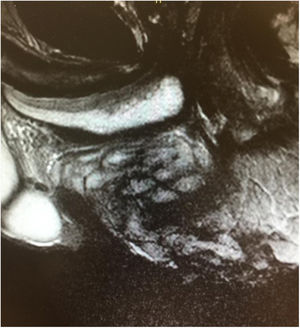

Varón de 53 años, ciclista aficionado que presenta una gran tumoración perineal de 10cm, blanda y recubierta de piel sana (tercer testículo, higroma isquiático o testículo accesorio) (fig. 1). Lesión infradiagnosticada, característica de ciclistas varones, producida por la fricción continua del tejido blando perineal entre la tuberosidad isquiática y el sillín. Suele presentarse como uno o varios nódulos en rafe medio o lateralizados. En la RMN (fig. 2) se objetiva alteración de la grasa perineal en forma de tractos fibrosos que protruye hacia el periné. El tratamiento de elección es su exéresis. Destacar la importancia de la sospecha clínica mediante una correcta anamnesis.